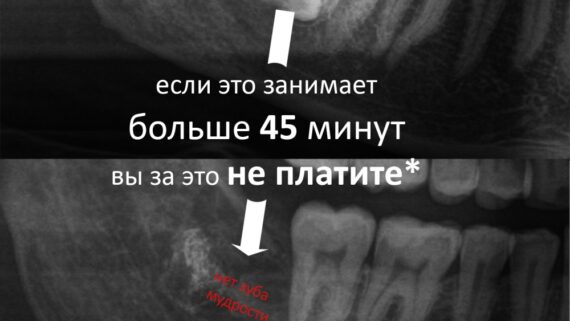

И все. Вся эта работа заняла, максимум, 15 минут. Если кто-то в этом сомневается, есть два варианта проверить:

И вот сегодня один из комментаторов, которому я сказал, что удаление зубов мудрости занимает, в среднем, 10-15 минут, попытался обвинить меня во лжи. В ответ я пригласил его в нашу клинику и предложил увидеть все лично. Он, как я понял, отказался.